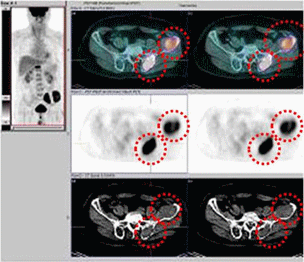

[ 다발성골수종 환자의 양전자방출단층촬영 ( PET ) ]

양전자방출단층촬영(PET CT) 검사를 통해 골수종의 침범 위치를 알 수 있으며, 특히 골수 외 병변이나 예상하지 못했던 골 병변을 찾아내는데 도움이 됩니다.